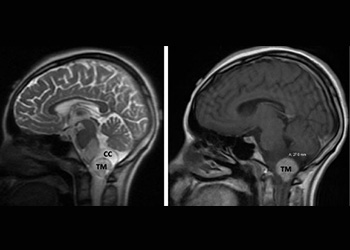

Hydrocephalus and Brainstem Tumor

Author: Jonathan L. Brisman M.D., F.A.C.S., Read More!